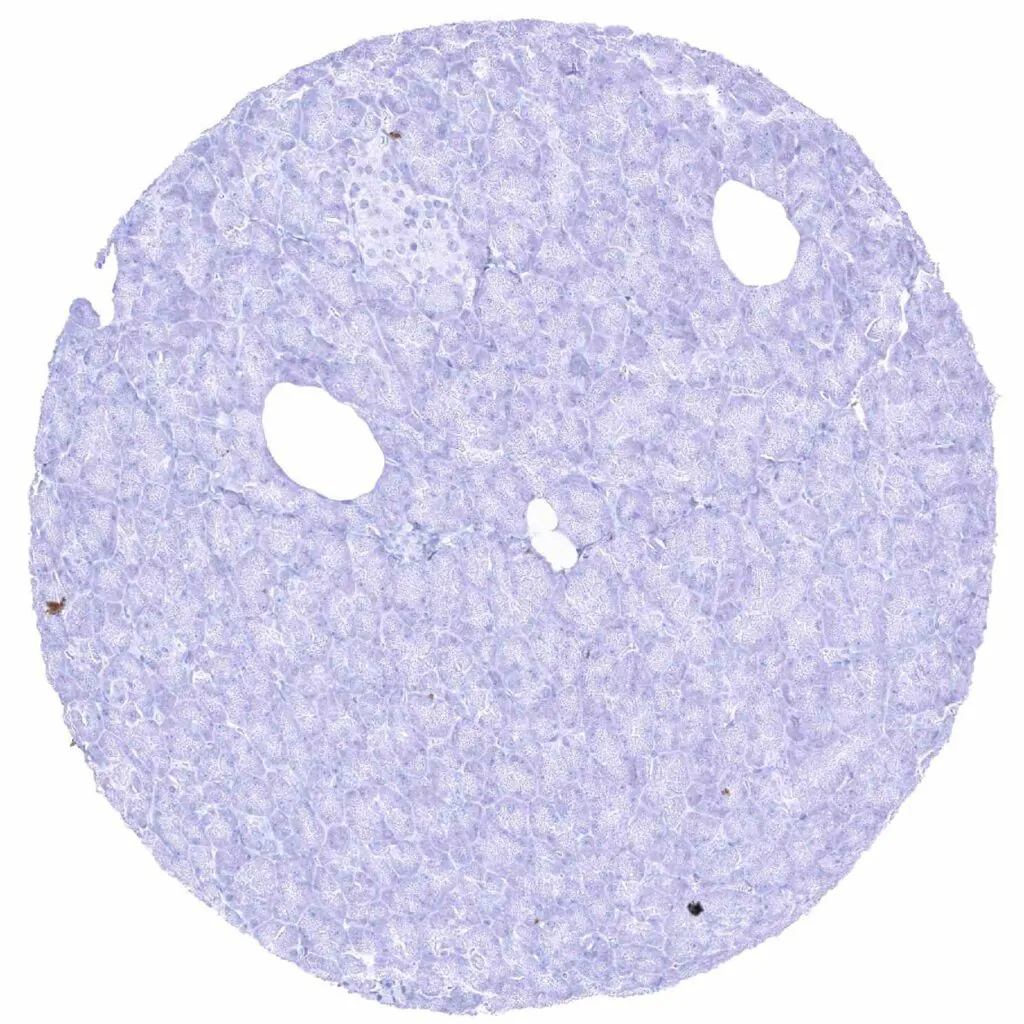

Spleen